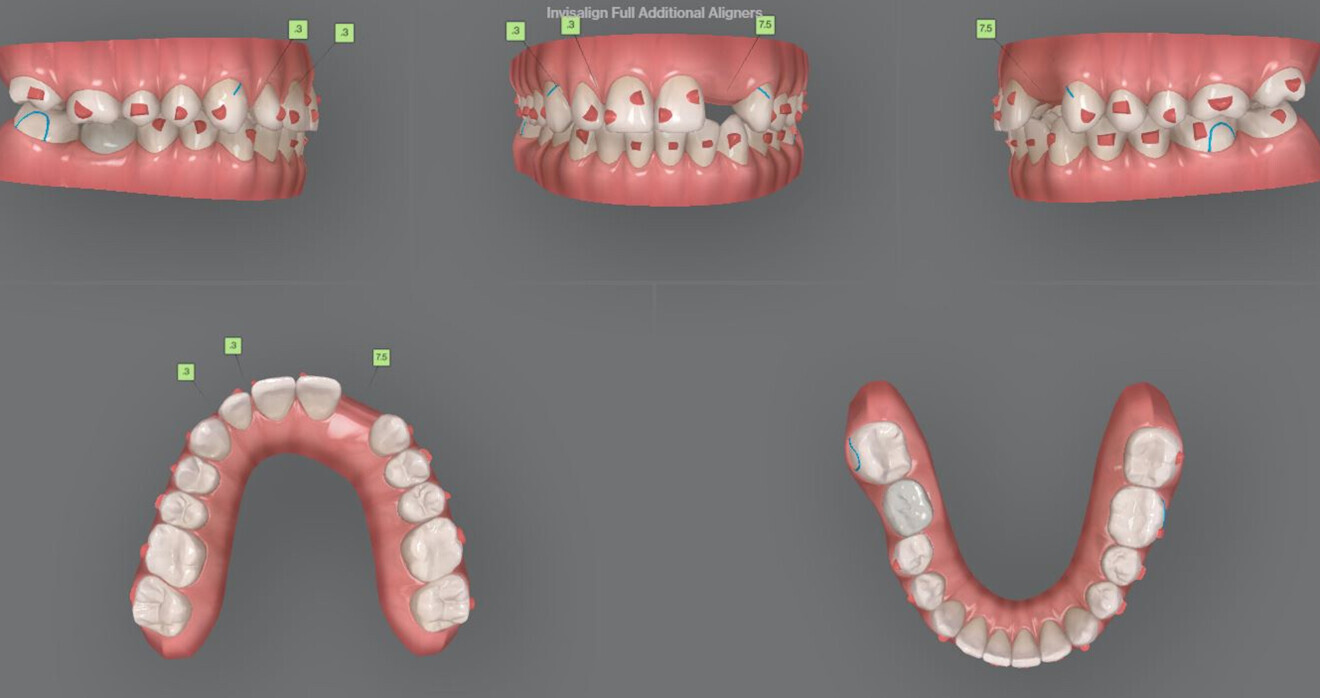

Fig. 5: The approved initial treatment plan.

This case was treated with the Invisalign system of aligners (Align Technology). The approved initial treatment plan included 49 aligners with distalisation of maxillary posterior teeth to Class I (approximately 3.5 mm; Fig. 5). A space of 6.5 mm in the area of the missing lateral incisor was planned for the implant, and interproximal reduction was planned in the mandibular anterior region. On the right side, the button cut-out for the Class II elastics was placed on tooth #47 instead of tooth #46, to avoid damage to the implant crown.